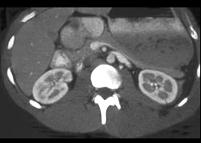

男,38岁,有外伤史,请根据所示图像,选择最可能诊断 ( )A、肾碎裂B、双肾未见异常C、肾挫伤D、微小的肾裂伤E、肾皮质缺损

问题 男,38岁,有外伤史,请根据所示图像,选择最可能诊断 ( )

选项 A、肾碎裂 B、双肾未见异常 C、肾挫伤 D、微小的肾裂伤 E、肾皮质缺损

答案 D